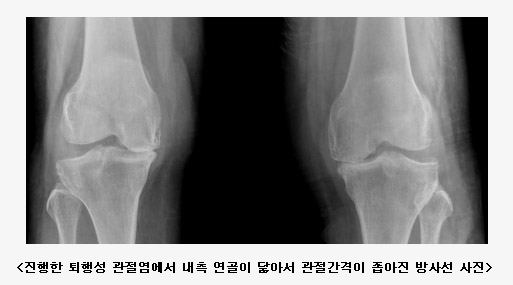

°ñ°üÀý¿° (ÅðÇ༺ °üÀý¿°) À̶õ?

ÅðÇ༺ °üÀý¿°À¸·Î ÈçÈ÷ ºÒ¸®¿ì´Â °ñ°üÀý¿°Àº Àü¼¼°èÀûÀ¸·Î °¡Àå ÈçÇÑ °üÀýÁúȯÀ̸ç, ³ëÀε鿡¼ ±â´É Á¦ÇѰú ÅëÁõÀ» À¯¹ßÇÏ´Â °¡Àå ÈçÇÑ ¿øÀÎÀÌ´Ù. °ñ°üÀý¿°Àº °üÀý ¿¬°ñÀÇ ÅðÇ༺ º¯È¿Í ¹ÝÀÀ¼º ½Å»ý°ñ Çü¼ºÀ» Ư¡À¸·Î ÇÏ´Â ÁúȯÀÌ´Ù. °í·É¿¡¼ ÁÖ·Î ¹ß»ýÇϰí, 45-55¼¼¿¡¼´Â ³²³à°£ Â÷À̰¡ ¾øÁö¸¸, 55¼¼ ÀÌÈÄ¿¡´Â ¿©ÀÚ¿¡ ¸¹´Ù. ¹«¸°üÀý°ú ¼Õ(¿øÀ§Áö °üÀý, ¾öÁö ¼Õ°¡¶ô ±âÀúºÎ)ÀÇ °ñ°üÀý¿°Àº ¿©¼ºÀÌ ´õ ¸¹°í, ºñ¸¸°ú °ü·ÃµÈ´Ù. ¾ûµ¢ÀÌ °üÀýÀÇ °ñ°üÀý¿°Àº ³²¼ºÀÌ ´õ ¸¹À¸³ª, ¿ì¸®³ª¶ó¿¡¼´Â ¾ûµ¢ÀÌ °üÀýÀÇ ÀÏÂ÷¼º °ñ°üÀý¿°Àº µå¹°´Ù. °ñ°üÀý¿°ÀÇ À§ÇèÀÎÀÚ´Â ³ªÀ̰¡ °¡Àå °·ÂÇÑ ÀÎÀÚÀ̸ç, ¿©¼º, ºñ¸¸, °üÀýÀÇ ¹Ýº¹ÀûÀÎ °ú´Ù»ç¿ë, °üÀý ¼Õ»óµîÀÌ ÀÖ´Ù.